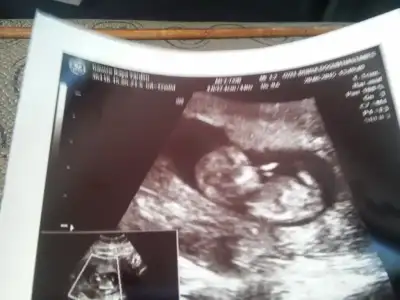

Buda fotomuzz:anneadayı::KK200:

Bebisim 12 haftadaymis benim hesabima gore 3 gun ondeyiz sata uyumluymus ama cok sukur....

Ense kalinligi 1.27 mm sanirim boy uzunlugu oluyo crp 50.65mm cikti..

Püüüüüh maşşallahhh teyzesi dötünü yesinn, ben pipi gördüm sanki bana mı öyle geldiiii. Ah nasıl kocaman olmuş maşşallahhhhh :) Rabbim sağlıkla koklamayı nasip etsinn innnnşallah :))

Birde boyle hareketleri yuzuyo gibiydi nasil desem poposunu kaldiriyodus sanki hafif hafif ay ne seker oluyo bu sipalar yaa :P